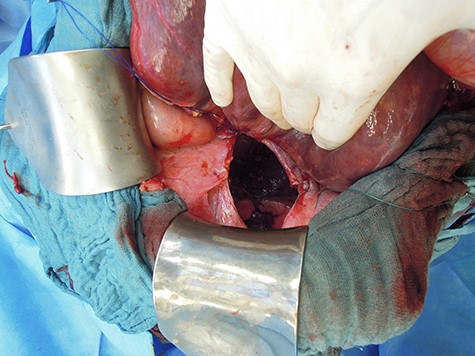

Intraoperatively, the defect could be closed by direct single stitch suture using a non-resorbable, braided thread, reinforced with a Parietene composite® mesh (Figs 3 and 4), a macroporous polypropylene mesh covered with an absorbable synthetic film. Further abdominal inspection was inconspicuous. Tension-free closure of the abdomen was performed. Event-free extubation postoperatively, the standard postoperative X-ray after intraoperative chest tube placement was unremarkable.

Revision laparotomy was performed, which showed a large diaphragmatic hernia on the right with intrathoracal right liver lobe, small bowel and colon (Fig. 5). The left-sided suture and mesh augmentation remained intact (Fig. 6). Due to the extended defect, only partial tension-free closure was possible, a Parietene composite® mesh was used (Figs 7 and 8) for bridging. Because of high intraabdominal pressure, primary abdominal wall closure was not possible; a gradual closure with an initially bridging vicryl mesh and vacuum therapy was performed (Fig. 9).